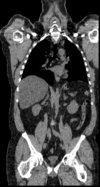

lleft whole body CT baseline lleft whole body PET baseline lleft whole body CT follow-up lleft whole body PET follow-up

CT: 512 x 512 x 267

0.97 x 0.97 x 3.27 mm

PET: 128 x 128 x 267

4.7 x 4.7 x 3.3 mm

CT: 512 x 512 x 195

0.98 x 0.98 x 5.0 mm

PET: 168 x 168 x 195

4.1 x 4.1 x 5 mm